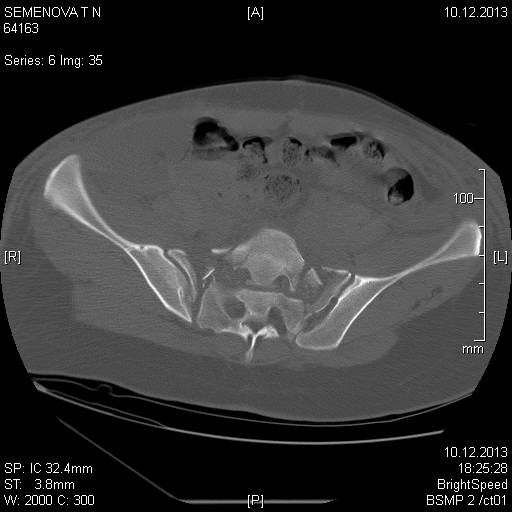

Доброго времени суток коллеги! Прошу вас подсказать тактику в решении оперативного лечения следующего сложного повреждения таза. Был ли опыт в фиксации подобных повреждений? Травма 03.12.2013,больная переведена из лечебного учреждения соседней области.На данный момент у больной следующий диагноз: ЗЧМТ,сотрясение головного мозга;Закр. травма грудной клетки,множественные переломы ребер справа с повреждением ткани легкого,правосторонний гемопневмоторакс,состояние после торакоцентеза;Закр.травма живота,разрыв селезенки,гемоперионеум, состояние после лапаротомиии спленэктомии;Закр. оскольчатый перелом сред-верх\3 левой бедренной кости, состояние после накостного металлостеосинтеза; Закр.поперечный переломовывих на уровне S1S2, многооскольчатый перелом латеральных масс крестца с обеих сторон,перелом обеих лонных и седалищных костей. Перелом поперечных отростков L1,L2,L3,L4, L5 позвонка. ШОК 3ст. Вкратце изложил диагноз. В настоящее время состояние больной тяжелое. Первым этапом планируем наложить АНФ (переднюю раму) После стабилизации состояния необходимо будет выполнить фиксацию: . Имеется один вопрос - какие импланты необходимы т.е. в какой комбинации и какая последовательность фиксации?

Добрый день! Станислав! Повреждение таза действительно тяжелое. В данном случае по мимо перелома передних колонн, что не самое страшное, имеется H-образный перелом крестца со смещением каудальной части. перелом поперечных отростков подтверждает вертикально нестабильный характер травмы таза. Предложенная конструкция действительно является вариантом решения проблемы,а скомпоновать ее можно из любого транспедикулярного фиксатора той фирмы которая работает у вас с нейрохирургами.Но помимо этого необходимо выполнить декомпрессию корешков конского хвоста. в противном случае та неврология которая есть и сейчас останется на всю жизнь. Судя по тяжести состояния к лечению перелома крестца сможете приступить не скоро, скорее всего на данный момент доминирует легочный дисстресс синдром, наверняка есть анемия после гемопневмоторакса, лапаротомии и накостного остеосинтеза бедренной кости.Поэтому когда дойдет дело до крестца репонировать отломки будет весьма сложно. Мы бы начали с остеосинтеза ребер, чтобы сделать пациента мобильным, передние колонны можно фиксировать перкутанно винтами, сзади кроме илиолюмбальной конструкции, ляминэктомия с целью декомпрессии, репозиция и дополнительная фиксация реконструктивными пластинами, лучше LCP. Пригласите на операцию нейрохирурга-вертебролога. Успехов.

В данном случае кроме фиксации крестца требуется декомпрессия канала. А вправленный вывих надо удержать, и вертикальные пластины с юникортикальной возможностью в 2.7 мм помогут создать стабильность. Кроме этого, надо создать условия по предупреждению компрессии крестца с двух сторон. В связи с тем, что процедура заканчивается в области крестца, а также наличие повреждения позвонков, это ограничивает возможности педикулярной фиксации. Мне кажется, от боковой компрессии лучше удержала бы согнутая по контуру крыла узкая в 4.5 мм балка-пластина.